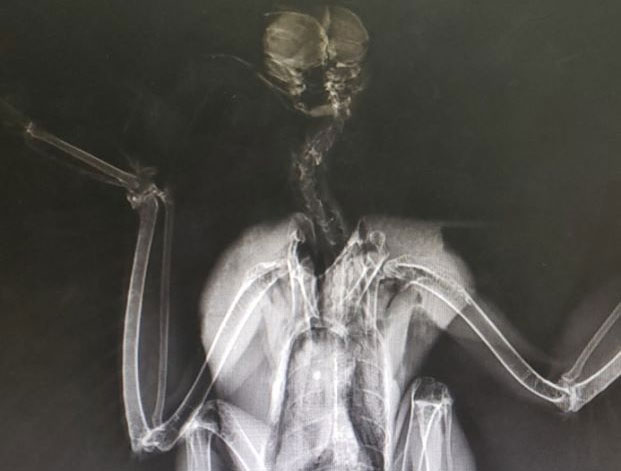

Digital Radiology

Digital x-rays assist in diagnosing illness & injury.